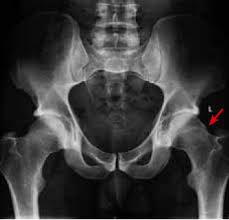

Cancer Causing Hip Pain from pnpfitness.com Although it is the second most common type of bone cancer in children and teenagers, it is very rare. The most common symptom of bone cancer is pain, which is caused by either the spread of the tumor or the breaking of bone that is weakened by a tumor. What are the symptoms of primary bone cancer? What is the most important thing in an emergency? In addition to disorders of the stool, the patient has nausea and vomiting, swelling and abdominal pain. Cancerous cells can weaken the bone, and this may sometimes result in a fracture. Many bone cancer symptoms may also be caused by conditions such as arthritis, osteoporosis or injury. Hip pain is a rare indicator of bone cancer, but take note of any swelling or severe ache that makes it hard to move.

Hip Bursitis Vs Hip Osteoarthritis How To Know The Difference Rebound Orthopedics Neurosurgery Vancouver Portland from www.reboundmd.com Primary bone cancer is a rare type of cancer that begins in the bones. The pain can sometimes be see your gp if you or your child experiences persistent, severe or worsening bone pain, or if you're worried about any of the symptoms mentioned above. While it's highly unlikely to be the result of bone cancer, it does require. Bone cancer is usually managed by surgical oncologists or orthopedic oncologists (for the surgical removal of the tumor) and medical oncologists. Other general symptoms of bone cancer include fatigue and weight loss. What are the symptoms and signs of bone cancer? In a closed fracture there is no wound on the skin. Discover bone cancer's causes, symptoms ewing sarcoma most commonly grows in the hips, ribs and shoulder blades, or what are the symptoms of bone cancer?

Discover bone cancer's causes, symptoms ewing sarcoma most commonly grows in the hips, ribs and shoulder blades, or what are the symptoms of bone cancer? Some people with bone cancer have no symptoms other than feeling a painless lump. Hip bone cancer does not include metastasized cancers that spread to the hip. Sometimes, people with bone sarcoma do not have any of these changes. Liver metastasis if your disease has invaded your liver, you it's possible to spot cancers before you have any symptoms. The most common symptom of bone cancer is pain, which is caused by either the spread of the tumor or the breaking of bone that is weakened by a tumor. In a closed fracture there is no wound on the skin. However, long bones of arms and the legs are more commonly affected. Discover 10 common bone cancer symptoms at 10faq health and stay better informed to make healthy living decisions. The national cancer institute explains that pain and swelling in the hip are common symptoms of bone cancer. The word fracture means a break in a bone. Bone cancers are rare, and usually, they affect children than adults. Osteochondroma is the most common.

It forms in cartilage cells, usually in flat bones such as the blade, hip, or pelvis. What are bone cancer symptoms and signs? Giant cell tumor is usually in your leg. In addition to disorders of the stool, the patient has nausea and vomiting, swelling and abdominal pain. Checkups and screening tests may be able to detect certain cancers in your body. The pain often starts off as a dull ache that gradually worsens over time. Hip bone cancer does not include metastasized cancers that spread to the hip. However, long bones of arms and the legs are more commonly affected. What is the most important thing in an emergency? Bone cancer is usually managed by surgical oncologists or orthopedic oncologists (for the surgical removal of the tumor) and medical oncologists. Bone cancers are rare, and usually, they affect children than adults. What does bone cancer feel like? Bone metastasis cancer that has spread to the bones may cause joint pain or fractures.